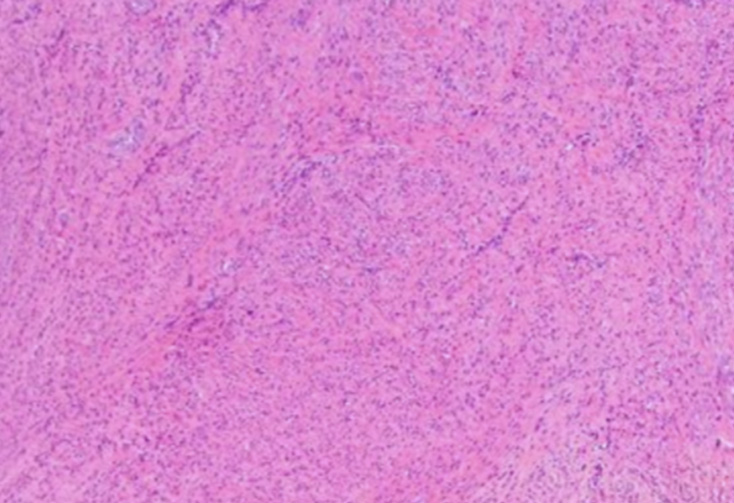

A portion of the sigmoid mesentery involving the mass was removed. The tumor, which appeared to originate from the uterine fundus, was completely resected and sent to pathology. A total abdominal hysterectomy and bilateral salpingo-oophorectomy were performed. The abdomen was examined for additional sites of metastasis, but none were identified. The abdomen was closed using #1 looped Polydiaxanone sutures. The wound was irrigated with saline and subsequently closed with a skin stapler. The patient tolerated the procedure well and was extubated without complications. Pathology demonstrated that the mass was an aggressive-behaving uterine leiomyoma (Figure 1). Additionally, ascitic cytology was negative for malignant cells.

Figure 1: Pathological examination of the mass was consistent with a uterine leiomyoma.